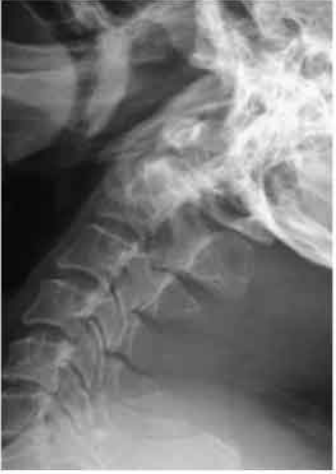

C1-C2 was reducible on extension and held in position on the operating table. Laminectomy was not required in this situation.

C1-C2 was maintained in extension with C1-C2 trans articular screw fixation with additional wiring of the posterior arch of C1 to C2 and bone grafting was done.